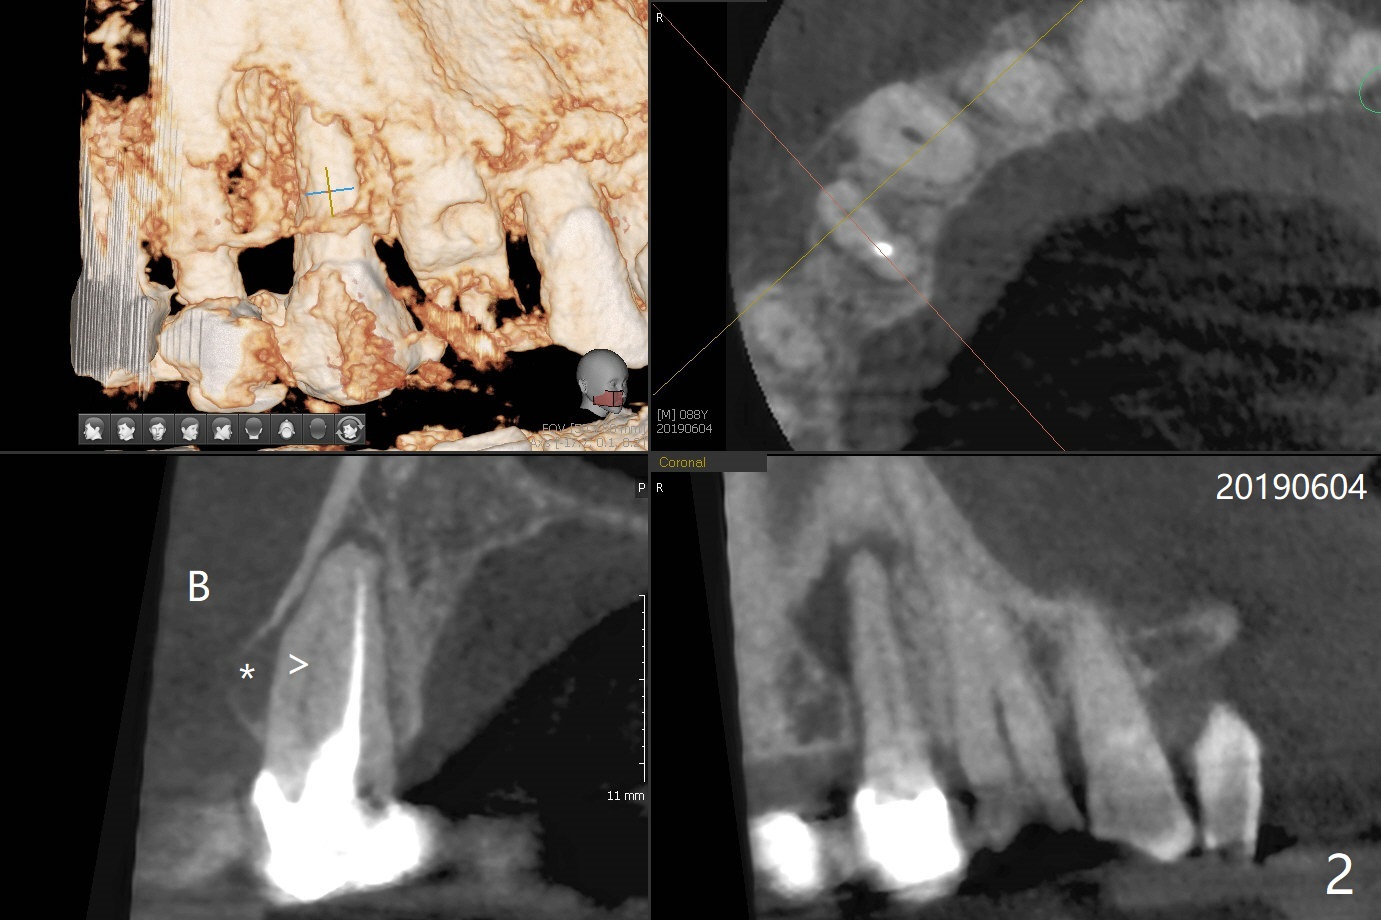

A 90-year-old man (bruxer) has porcelain fracture at #4. PA happens to reveal large PARL at #5 (Fig.1). CT taken a year ago shows missing buccal canal (Fig.2). Bone loss seems to be extensive (Fig.3,4 (root fracture?)). Access to the canal through PFM fails; the crown has to be removed (Fig.5). Fortunately the buccal canal is found and negotiable.